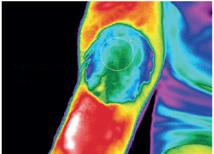

I alle tre forsøg blev deltagernes tryksmertetærskel (det tryk hvor deltagerne begyndte at føle at et tryk

ind på deres skinneben blev smertefuldt) målt og deres smerteudholdenhed undersøgt ved hjælp af en kuldetest (en test hvor deltagerne skulle holde deres hånd i et kar med 0 grader koldt vand i op til to min.). Deres evne til at modulere deres smerte blev målt som ændringen i tryksmertetærskel fra før til efter kuldetesten.

QST-interventioner

Manuel: Deltagerne blev guidet igennem forsøget af en forskningsassistent, og tryksmertetesten blev udført manuelt.

Auto: Her var ingen til stede, men deltagerne blev guidet igennem forsøget via en video på en computer, og tryksmertetesten blev udført via en robot.

Guidet: Deltagerne blev guidet igennem forsøget af en forskningsassistent, men tryksmertetesten blev udført via en robot.

De fire prisvindere har to og to skrevet to selvstændige specialer. Det ene undersøgte forskellen mellem manuel og auto, og det andet undersøgte forskellen mellem auto og guidet med det formål at undersøge, om der var forskel på deltagernes smertemodulering ved social isolation sammenlignet med en situation med klinisk interaktion.

Deltagerne blev allokeret i én af tre QST-interventioner i et randomiseret kontrolleret studie. Deltagerne blev efterfølgende testet i en situation med enten social isolation guidet af video, i en situation med klinisk interaktion guidet af en forsknings-

assistent eller blot ved tilstedeværelse af en forsøgsassistent. Smertemodellering responset blev undersøgt ved brug af en test for tryksmertetærsklen, udført ved et tryk på Musculus Tibialis Anterior, samt en kuldetest udført på hånden.